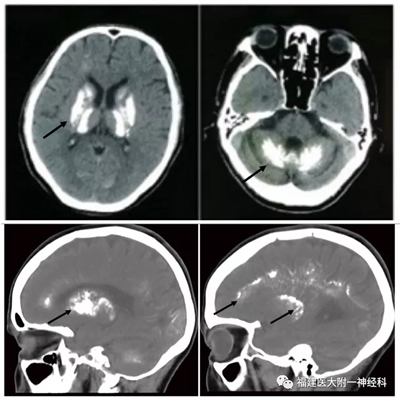

据介绍,PFBC是一种家族遗传性疾病,以双侧基底节、小脑或其它脑区病理性钙化沉积为特征,其临床症状主要包括进行性运动障碍、神经精神症状、构音障碍和认知障碍等,此病在老年人中发生率高达20%,由于其发病机制不清楚,临床上缺乏有效的治疗手段。虽然此前已探明了4个PFBC致病基因,但仍有50%以上的家族性患者的致病基因尚未明确。我院院神经内科与国内多家医疗单位合作,于近年收集了50余个PFBC家系,通过全外显子测序,在来自福建、山东、安徽、四川等地的6个隐性PFBC家系中,发现MYORG 基因突变,并进一步在基因敲除的小鼠脑内观察到了脑钙化结节的形成,通过扫描电镜结合X射线能谱仪分析,发现钙结节的主要成分为钙、磷,与临床病人脑钙化的元素组分高度相似。

据了解,此前发现的PFBC四个基因均为显性遗传,而该工作所发现的MYORG基因在PFBC中呈隐性遗传,在所有的PFBC家系中,MYORG突变比例达11%,为本病第二常见致病基因。有趣的是,MYORG突变在隐性家系中所占比例高达50%。在机制层面,之前研究认为脑钙化主要由周细胞及血脑屏障破坏所致,而本研究首次表明胶质细胞也是脑钙化发生的关键因素。本研究进一步丰富了PFBC致病基因谱,为其基因诊断奠定了基础,同时为其发病机制及治疗研究提供了新的线索。

MYORG基因敲除小鼠大脑内出现钙磷物质沉积